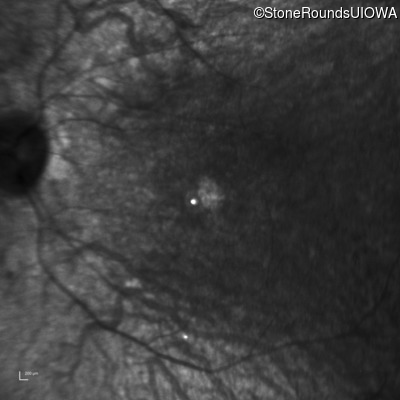

Infrared Fundus Photograph - Right - 5/180

Exemplar